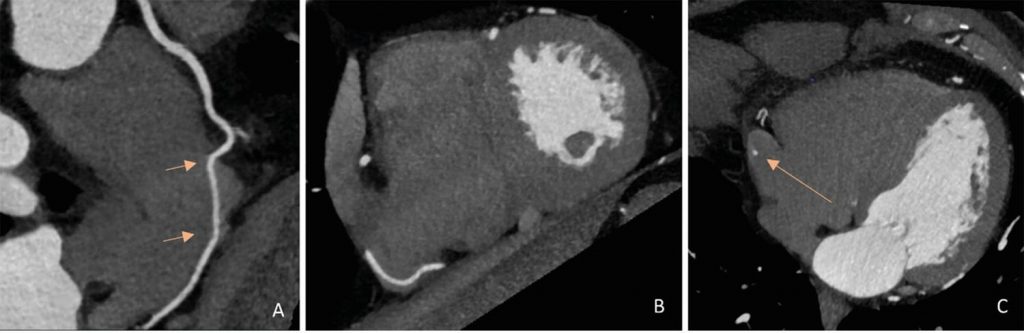

A ATC mostrou a origem normal dos troncos das coronárias direita e esquerda, e não havia evidência de doença arterial coronariana obstrutiva. A artéria coronária direita proximal (CD) tinha um trajeto epicárdico normal, mas notou-se que a mediana penetrava na parede atrial direita por um trajeto de 30 mm dentro do átrio direito, saindo para seu trajeto usual no sulco atrioventricular posterior, conforme demonstrado via as imagens de TC de reconstrução multiplanar na projeção de intensidade máxima ( ), bem como as reconstruções tridimensionais ( ).